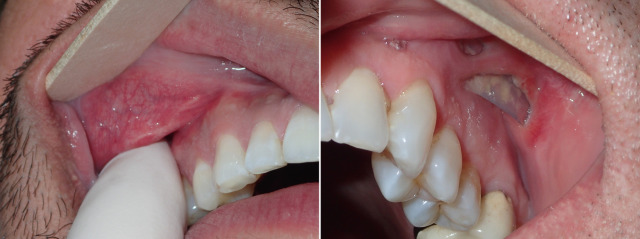

During preoperative evaluation, it is also important to evaluate the patient’s oral health. Placing implants in the presence of dental or periodontal disease can severely compromise the case and result in infection ( Fig. 7.6 ). Patients with oral disease must be treated to achieve a normal state of oral health prior to implant placement. All implant patients require a panoramic radiograph or computed tomography (CT) scan to rule out any osseous or dental or sinus pathology.

Infection has been an uncommon experience. It usually manifests in the first week or two after surgery. Infection generally presents as one side failing to heal, pain, increased swelling, periorbital edema, and purulent drainage with a bad taste in the mouth ( Figs. 7.44–7.46 ). The incision site will frequently be very inflamed and sometimes open. It is possible to salvage a minor infection with open incision and drainage, irrigation, and systemic antibiotics. If an implant becomes infected and is secured with screw fixation, I will attempt salvage with incision and drainage, antibiotic rinses, and systemic antibiotics. The lack of mobility assists in healing. In my experience, attempting to salvage a mobile, unfixated implant is futile and should not be attempted. Resistant infections warrant implant removal, and the implant can be replaced after healing. Because the explanted site will have scar tissue and remnant implant capsule, the result is sometimes unnoticeable. On occasion, I have taken out a single implant and not replaced it, without any noticeable cosmetic deficit. In other cases, the deficient side is noticeable and must be reimplanted.